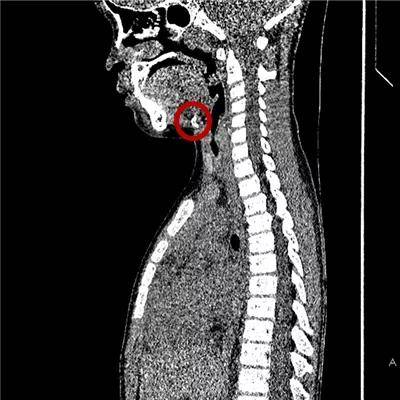

7岁·鸡骨头

吞入鸡骨头,横看呈线,侧成点峰。

尤其是尖锐的鸡骨、猪骨、鱼刺,一旦卡住,非常容易戳穿消化道。